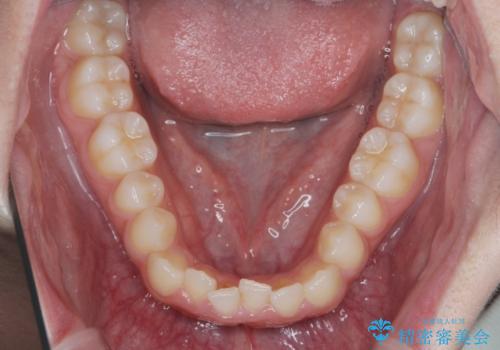

前歯のガタつき・ねじれを治すマウスピース矯正

- 前歯のねじれ、ガタつきを改善し綺麗な歯並びにしたいと希望され来院されました。

マウスピース矯正インビザラインによる矯正治療を計画しますが、マウスピース矯正で治りにくい歯のねじれを事前にワイヤー矯正でしっかりとなおしておくことで矯正治療期間の短縮できるような治療計画を立てます。

マウスピース矯正を始める前にワイヤー部分矯正を行ったことで改善のしにくい歯のねじれをしっかりと治すことができました。